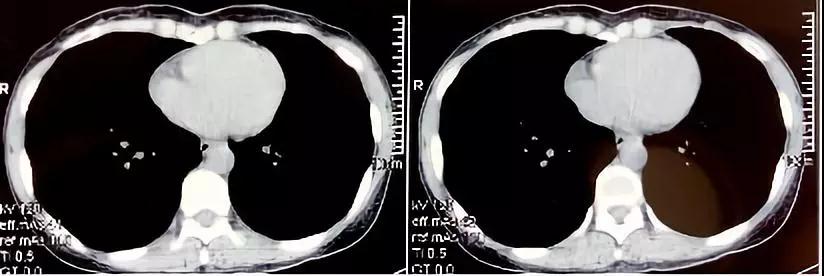

16层螺旋ct多种重建方法在诊断肋软骨骨折中的应用 罕见病 疑难病 会诊平台 专家会诊 网上会诊 医学影像

128层螺旋ct三维重建在胸部外伤肋骨及肋软骨骨折诊断中的应用 中国期刊网

多层螺旋ct后处理重建在肋骨和肋软骨骨折诊断中的临床应用 中国期刊网

医院动态 放射科利用多层螺旋ct后处理重建技术诊断肋软骨骨折 药最网 Www Yaozui Com

16层螺旋ct多种重建方法在诊断肋软骨骨折中的应用 罕见病 疑难病 会诊平台 专家会诊 网上会诊 医学影像

16层螺旋ct多种重建方法在诊断肋软骨骨折中的应用 罕见病 疑难病 会诊平台 专家会诊 网上会诊 医学影像